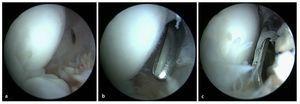

Fig. 8 a) Mediante un artroscopio estándar (ángulo visual de 30º) es posible visualizar el compartimento anterior. Primero se observa el húmero distal (1), la cabeza del radio (2) y el tejido sinovial (3). b) A continuación se desplaza el artroscopio más hacia el interior del compartimento anterior. Aquí se pueden observar la tróclea humeral (1), el proceso coronoides (2) y el tejido sinovial (3). Con frecuencia se observan osteofitos (4) en la zona del húmero anterior, así como cuerpos articulares libres (5).

Fig. 9 La perforación del abordaje anteroulnar se realiza mediante una aguja canulada. a) Bajo visión artroscópica desde anteroradial se realiza en primer lugar la punción con la aguja en el portal anteriormente marcado. b) Si la aguja está correctamente posicionada, tras la incisión cutánea se procederá al corte romo con tijeras del tejido subcutáneo y de la cápsula. c) A través de este portal se introducirá a continuación un resector sinovial motorizado. A través del portal anteroulnar se puede quitar la membrana sinovial inflamada.

Fig. 10 Después de la sinovialectomía se extraen los cuerpos articulares libres. Según el tamaño de estos cuerpos, la extracción se realizará mediante pinzas o un resector sinovial.

Fig. 11 a, b) Los osteofitos en la zona del proceso coronario se extraen con un cincel Lambotte. c) Los fragmentos osteocondriales se extraen de la articulación con una pinza de agarre. d) El proceso coronoides remanente se alisa con el resector sinovial o una fresa de bola (no representado en la imagen).

Fig. 12 Las formaciones osteofíticas del borde del húmero anterior se pueden extraer progresivamente con una fresa de bola.